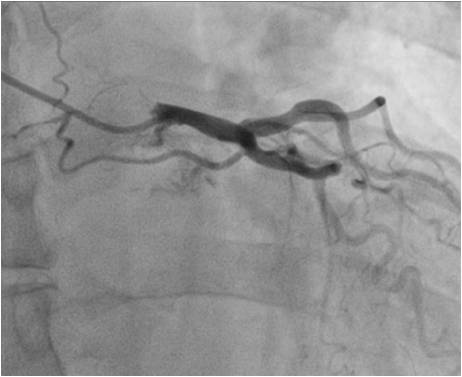

In the process of laboratory and instrumental examination, according to the results of multispiral CT-angiopulmonography, the central form of PE was diagnosed (Figure 1), for which thrombolytic therapy with actilyse (Аlteplase®) was performed.

Fig. 1. Fragments of multispiral СT-angiopulmonography in coronal (A, D), axial (B) and sagittal (C, D) projections: оcclusive thrombotic masses are determined at the level of the right branch of the PA (A, B, C); stenosing thrombotic defects of the left main branch and the left lower lobe branch of the PA (E).

Notes: CT — computed tomography, PA — pulmonary artery.